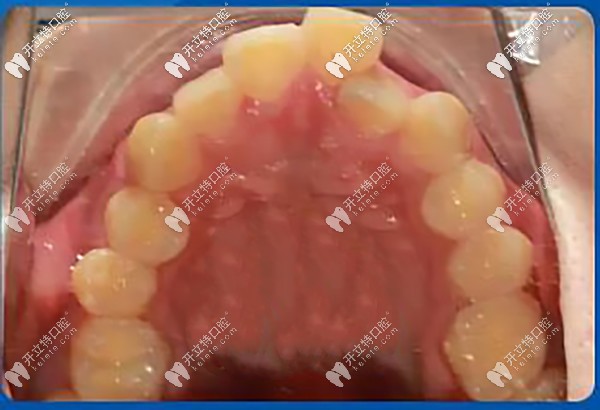

從口內(nèi)上頜照可以看到牙齒重度擁擠不齊,牙弓狹窄(尖圓弓形)。

牙齒重度擁擠不齊,牙弓狹窄